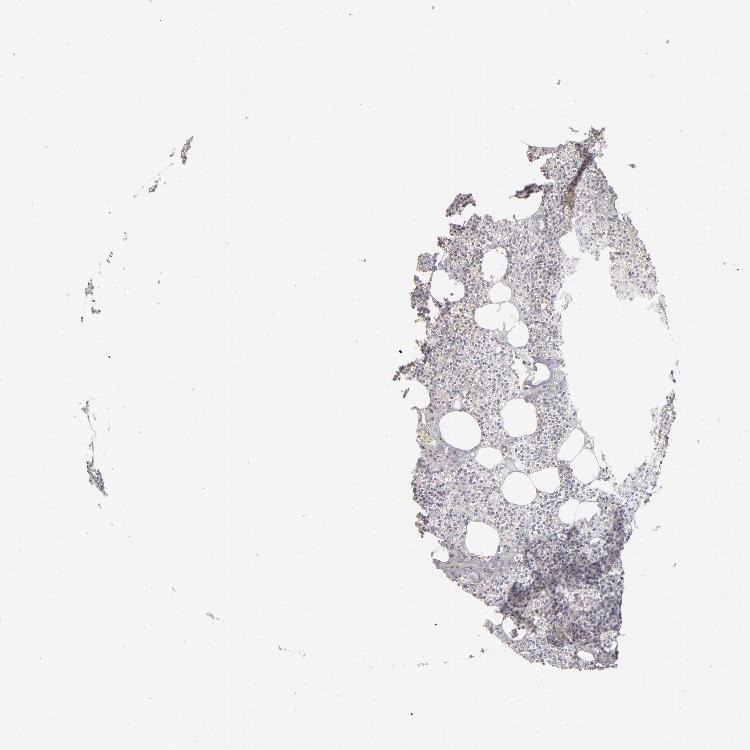

TISSUE PRIMARY DATA PARATHYROID GLAND Show tissue menu

PARATHYROID GLAND - Antibody stainingi

Antibody staining in the annotated cell types in the current human tissue is reported as not detected, low, medium, or high, based on conventional immunohistochemistry profiling in selected tissues. This score is based on the combination of the staining intensity and fraction of stained cells.

Each image is clickable and will lead to virtual microscopy that enables deeper exploration of all samples and also displays staining intensity scores, fraction scores and subcellular localization as well as patient and tissue information for each sample.

Antibody HPA002242Antibody CAB001513Antibody CAB019952Antibody CAB080301

Glandular cells LowMediumMediumMedium